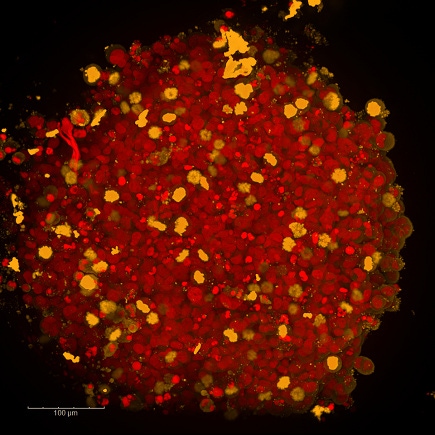

Maximum intensity projection image (20xW) of InSphero human liver microtissue stained with TMRM, imaged on the Opera Phenix high-content screening system.

Maximum intensity projection image (20xW) of InSphero human liver microtissue stained with CLF, imaged on the Opera Phenix high-content screening system.

Maximum intensity projection image (20xW) of InSphero human liver microtissue stained with CMFDA, imaged on the Opera Phenix high-content screening system.

Maximum intensity projection image (20xW) of InSphero human liver microtissue treated with FCCP (affects the hepatobilary transporter activity in these microtissues) and stained with CMFDA, imaged on the Opera Phenix high-content screening system.

Maximum intensity projection image (20xW) of InSphero human liver microtissue treated with FCCP (affects the hepatobilary transporter activity in these microtissues) and stained with CLF, imaged on the Opera Phenix high-content screening system.